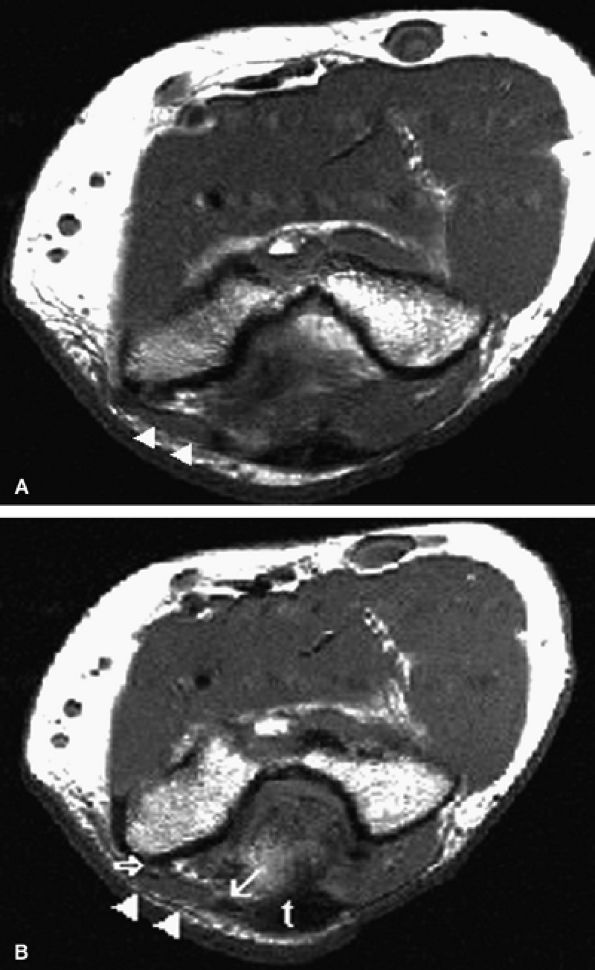

accentuated by elbow flexion. Congenital absence (Fig. 12.25), laxity or tear of the arcuate ligament, trochlear hypoplasia, and posttraumatic cubitus valgus deformity are all postulated etiologic factors of ulnar nerve instability. Snapping triceps syndrome, dislocation of the medial head of the triceps muscle over the medial epicondyle, has been implicated as an additional cause of ulnar nerve dislocation (Fig. 12.26).59,60

FIGURE 12.26 ● Medial head of triceps. Axial T1-weighed images depict a prominent medial head of triceps muscle (arrowheads) and tendon (arrow) at the level of the cubital tunnel (open arrow). Note blending of the medial head tendon with the main triceps tendon (t) on a more distal image, a feature distinguishing it from the anconeus epitrochlearis muscle.

|